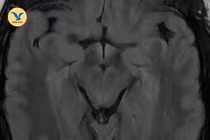

Nhìn mờ không ngờ huyết khối tĩnh mạch não

Theo BS. Trung Hiếu, cơ chế bệnh sinh của huyết khối tĩnh mạch não liên quan đến việc cục máu đông cản trở dòng máu tĩnh mạch, khiến áp lực trong não tăng.